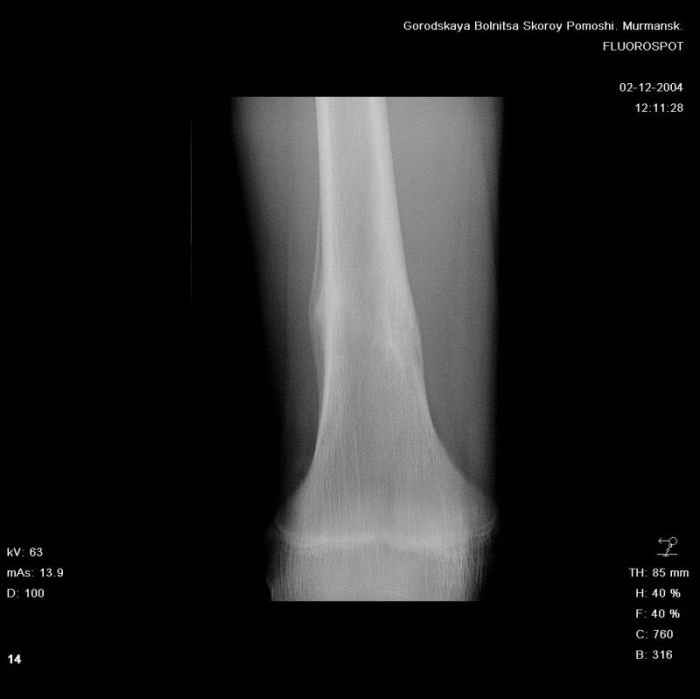

Здравствуйте, уважаемые коллеги!Представляю вашему вниманию интересный случай и пока что непонятный для меня в диагностическом плане. На днях в наше отделение (детской ортопедии и травматологии) поступил 13-летний мальчик по направлению из поликлиники с диагнозом: остеома нижней трети правого бедра.

Анамнез практически никакой: в следствие травмы (растяжение связок коленного сустава) от 07.11.2004 выполнены Rg-граммы в травмпункте и обнаружено опухолевидное образование. Первичные Rg-граммы я не публикую, так как они заметно худшего качества, да и динамики за прошедшие три недели не отражают. Болевой синдром купирован в течение трёх дней. В настоящий момент мальчика ничего не беспокоит. Ходьба не нарушена, опухоль пальпируется с трудом по задней поверхности в н\3 правого бедра, пальпация безболезненна, объем движений в суставах правой нижней конечности полный и симметричный. Кожа над опухолью не изменена.В нашей клинике проведено дополнительное обследование: общие анализы крови и мочи, биохимия крови без особенностей. Выполнены Rg-граммы на цифровом Siemens обычные и продольные томограммы срезами 3-5 мм, а также компьютерная томография поперечными срезами по 5 мм. Прошу обратить внимание, что на приведённых томограммах видны две полости 10х15 мм и 15х60 мм. Также имеются два опухолевидных образований наслаивающихся друг на друга: уплощённое и вытянутое 10х100 мм и элипсовидной формы 15х30 мм. Это хорошо заметно на фото a_1.jpg c_1.jpg и d_1.jpg. Плотность внутри полостей 125% от плотности костномозгового канала, плотность наружного опухолевидного образования 55% от плотности кортикального слоя. Также отмечается линия перелома по центру наружного опухолевидного образования.Исходя из полученных данных мнения в плане диагноза несколько разделились от 1)сочетания кортикальной фиброзной дисплазии и латентно протекавшего маршевого перелома н\3 правого бедра до 2)остеосаркомы. В отношении первого варианта не сходится отсутствие клиники при переломе такой крупной кости как бедро, второй вариант вообще оставлю без комментария, ибо некомпетентен. Хотелось бы услышать мнения коллег, с удовольствием ознакомлюсь с любыми предположениями и замечаниями.С уважением, Александр Е. КлоковОтделение детской ортопедии и травматологииБСМП г. Мурманска.